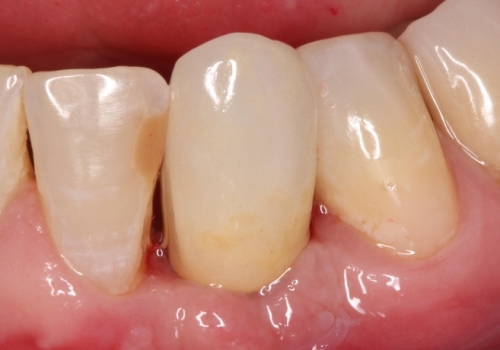

Stomatologiyanın təməl vəzifələrindən biri, itirilmiş dişlərin funksiya və estetik olaraq təbiiyə ən yaxın şəkildə bərpa edə bilməkdir. Dişsizliyin estetik və funksional olaraq yüksək səviyyədə reabilitasiyası, pasiyentlərin çeynəmə, danışma və gülmə kimi funksiyalarını qüsursuz icra edə bilməsi baxımından çox önəmlidir. Diş implantları xüsusi texnologiya hazırlanaraq, itirilmiş dişin bərpası üçün tətbiq edilən süni diş kökləridir. Bu metod təbiiyə ən yaxın bərpanı vəd edən müalicə metodu kimi uzun illərdən bəri beynəlxalq miqyasda geniş tətbiq olunur. İmplantasiya, bu işin peşəkarı yüksək ixtisaslı mütəxəssis tərəfindən qısa bir müddət davam edən prosedur vasitəsilə ağrısız, qısa müddətə və həyati funksiyaların məhdudlaşmaması şərti ilə həyata keçirilən müalicə üsuludur.

Dental implantlar əsasən titandan hazırlanır. Bu materialdan hazırlanmasının ən başlıca səbəbləri, bu metalın orqanizm tərəfindən rədd edilməməsi, heç bir allergik reaksiyaya səbəb olmaması və bu təyinat üçün yetərli möhkəmliyinin olmasıdır. Diş implantları vasitəsilə, tək diş əksikliyindən, çoxsaylı diş əksikliyi və tam dişsizlik halları funksional və estetik bərpa edilə bilir. İmplantın üzərinə hazırlanan diş konstruksiyaları müvafiq vəziyyətlərdə implantların tətbiqi ilə eyni gündə və ya müəyyən bir sağalma dövrünün keçməsindən sonra hazırlana bilir. İmplantların istismar müddəti, doğru planlama və icraat həyata keçirildiyində, eyni zamanda yetərli gigiyenik qulluq şəraitində bir neçə on illik bir periyodu əhatə edə bilir.